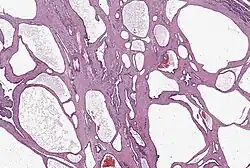

Histologie eines serösen Zystadenoms des Pankreas

Die serös-zystische Neoplasie, auch als seröses Zystadenom oder als mikrozystisches (Zyst-)Adenom bezeichnet, ist ein meist gutartiger Tumor (Malignitätsrisiko <5 %), der vorwiegend bei Frauen im höheren Lebensalter beobachtet wird. Er liegt häufiger im Pankreaskopf, jedoch kann jede Region betroffen sein. Zystadenome können 6 bis 10 cm groß werden. Sie bestehen im Unterschied zum muzinös-zystischen Tumor (s. o.) aus kleinen Zysten mit serösem Inhalt, die durch zarte Septen getrennt sind. Im Zentrum findet man eine narbenartige Verdichtung und oft auch Verkalkungen. Diese Zysten sind mit kubischem Epithel ausgekleidet, histologisch finden sich keine Atypien oder Mitosefiguren. Eine Assoziation mit dem Von-Hippel-Lindau-Syndrom wurde beschrieben, der Tumor kann dabei große Abschnitte der Bauchspeicheldrüse einnehmen. Das seröse Zystadenom weist keine Entartungstendenz auf und sollte nur entfernt werden, wenn es durch seine Größe Symptome verursacht.